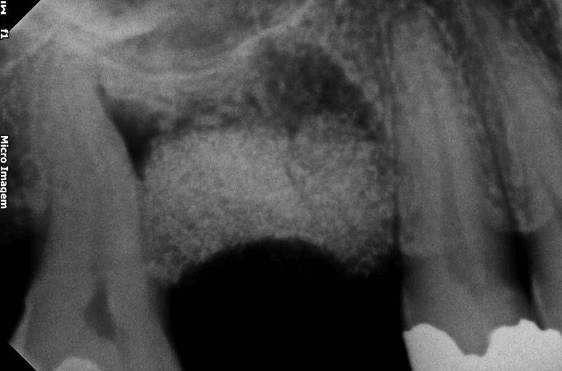

Avaliamos o desempenho do biomaterial de hidroxiapatita com colágeno tipo I (Extra Graft XG-13®) na manutenção do volume alveolar.

A aplicação como o caso clínico abaixo se mostrou uma técnica acessível a todos cirurgiões dentistas, pois se trata de um procedimento de simples execução e acessível. Logo, deveria constar na clínica diária.